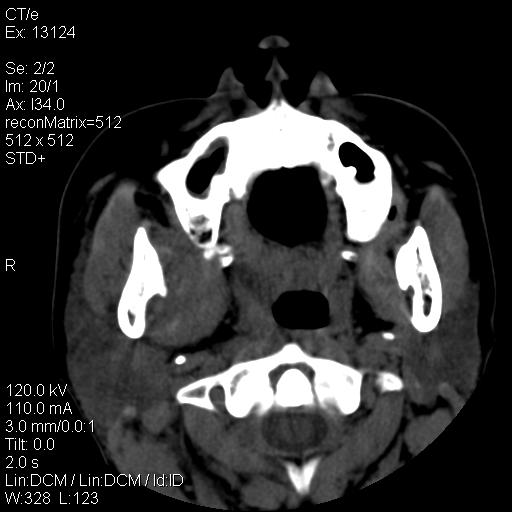

标题: CT18257:女,29岁,右下磨牙痛 [打印本页]

标题: CT18257:女,29岁,右下磨牙痛

女,29岁,右下磨牙痛,因产后2月,故未治疗。现右颌肿痛伴张口困难。请大家看看右侧鼻咽部、口咽部是否

zhichi 考虑  右侧颌下脓肿伴口咽鼻咽感染,淋巴结肿大。肿瘤待排

1)考虑右侧下颌区软组织脓肿(牙源性)。2)鼻咽部炎性改变;建议追踪复查。3)右侧上颌窦炎。4)双侧下鼻甲黏膜肥厚。

1)考虑右侧下颌区牙源性软组织脓肿。2)右侧上颌窦炎。3)双侧下鼻甲黏膜肥厚。4)鼻咽部炎性改变;建议追踪复查。